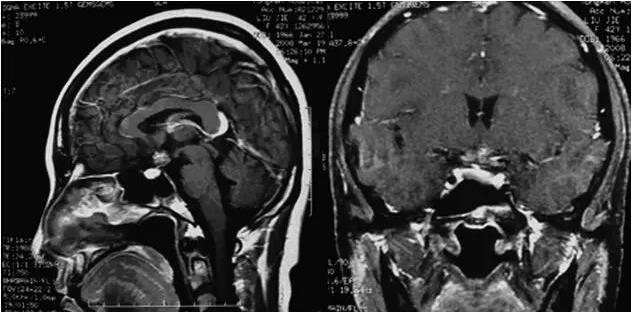

图1﹒12‐2头颅MRI

视交叉处可见一类圆形异常信号影,与视交叉分辨不清,信号混杂,内部可见短T1、短T2信号,大小约1.0cm×1.5cm×1.2cm,病变向后压迫垂体柄移位,增强后,病变不均匀性明显强化

脑内海绵状血管瘤可发生于中枢神经系统的任何部位,而发生在视交叉的海绵状血管瘤至今报道甚少。大部分视交叉海绵状血管瘤患者因视交叉出血而出现症状[5]。临床可表现为视交叉综合征或缓慢发展的双眼视力下降,也有报道单侧视力下降[6]。由于此病主要表现为视力损害,应与视神经病变、鞍上池的颅咽管瘤、垂体瘤、生殖细胞瘤、胶质瘤等相鉴别。本例患者临床表现反复双眼视力下降,每次急性起病,视力下降迅速而恢复较好,眼底检查视乳头形态大致正常,表现并非典型的视交叉综合征,因此在外院,此患者曾一直被误诊为“球后视神经炎”。球后视神经炎也称为特发性脱髓鞘性视神经炎,多为单眼或双眼的急性痛性视力下降,早期眼底正常,后期视乳头颞侧可苍白,视野为中心或旁中心暗点,通常预后较好,部分易复发。此患者反复双眼视力下降,但一直无伴发眼痛和转眼痛,每次视力恢复不完全,且视野表现不典型,应该引起警惕,临床表现不典型的病例应行头MRI检查排除颅内病变。该患者的头颅MRI表现视交叉处混杂信号,不均匀强化,符合海绵状血管瘤急性出血的表现。此患者手术后视力恢复欠佳,考虑与病史长、就诊时视神经已部分萎缩有关。